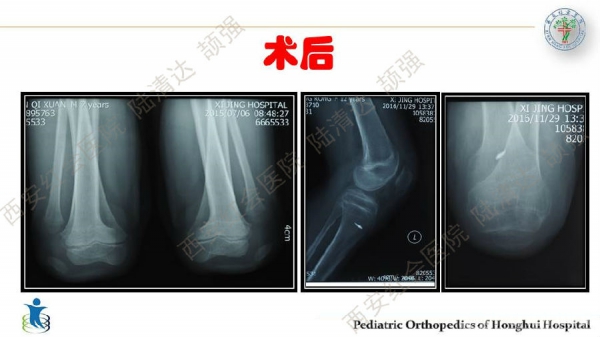

习惯性髌骨脱位,多见于儿童,女性多于男性。临床表现主要为行走步态难看、下肢无力、易摔跤等,而反复摔跤的病史常是患者就诊的主诉。其病理特点主要膝关节内外侧伸肌肌群不平衡及局部结构发育异常,表现为:股外侧肌及膝外侧软组织挛缩,髌韧带附着点偏外,股内侧肌群萎缩无力及MPFL发育不良,髌股关节滑车发育不良及膝外翻畸形等。习惯性髌骨脱位的治疗,建议早发现早治疗。不仅能有效解决脱位问题,还可避免继发畸形。如治疗延误,可出现髋、膝关节继发屈曲、腰前凸加大等畸形。甚至膝关节骨性关节炎,影响工作与生活。